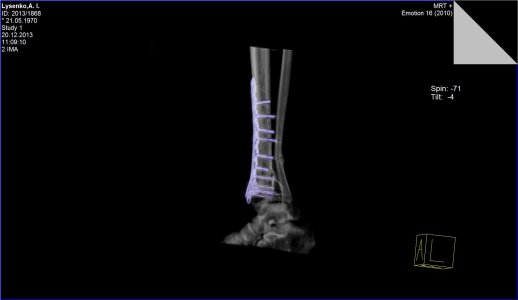

Здравствуйте. Меня зовут Андрей, мне 43 года. 5 сентября этого года меня травмировало на работе - перелом малой и большой берцовой кости со смещением. Операцию сделали 25 сентября, поставили пластину и наложили гипс. Через месяц врач-травмотолог гипс разрешил снять, но сказал, что нагрузку на ногу давать ещё рано. Очередное СКТ, которое я сделал 20 декабря показало, что кость до сих-пор не срослась. В настоящее время я всё-ещё хожу на костылях. Скажите пожалуйста имеет-ли вообще подобный перелом возможность срастись и если да, то сколько времени это может занять. Мой врач ни каких прогнозов дать пока не может и к сожалению ни какой информации мне по этому поводу не дает.